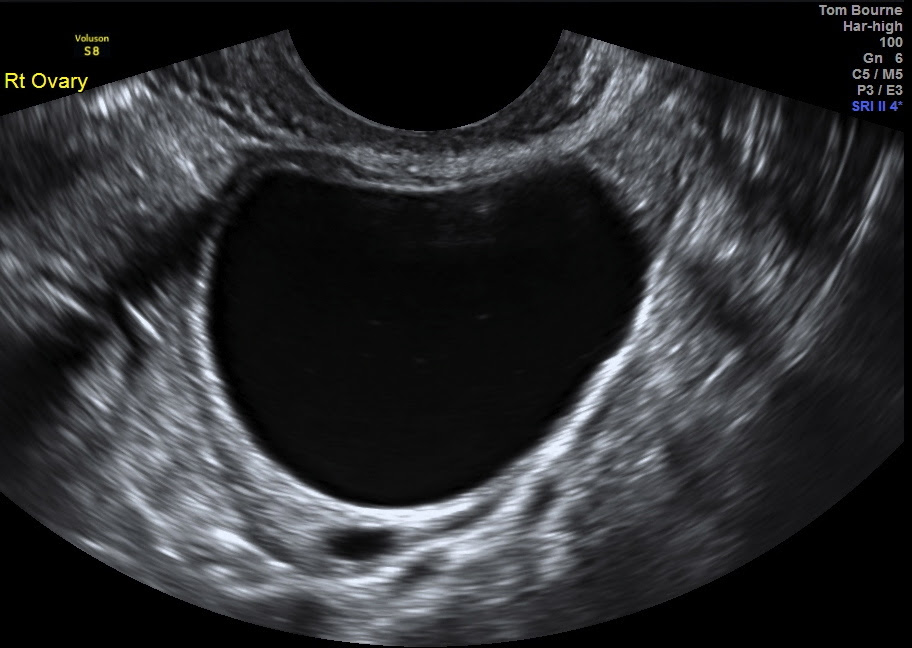

Transabdominal USS revealed a moderate amount of fluid in the abdomen and in the pouch of Douglas and a complex right adnexal mass with signs of peripheral vascularization (Figure 1).